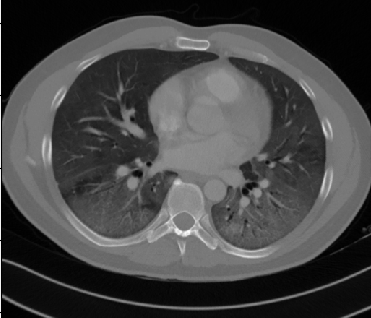

Some examples of CT slices from the cluster centers are given below. Figure 4 shows 10 consecutive slices from COVID-19 cluster center 0. Medical experts have annotated it as ’bilateral ground glass regions that appear, especially in lower lung lobes’. Figure 5 shows 10 slices from COVID-19 cluster center 2. According to medical experts’ annotation, this is consistent with ’COVID-19 pneumonia bilateral thickening filtrates’. Figure 6, on the contrary, shows 10 slices from non COVID-19 cluster center 9.